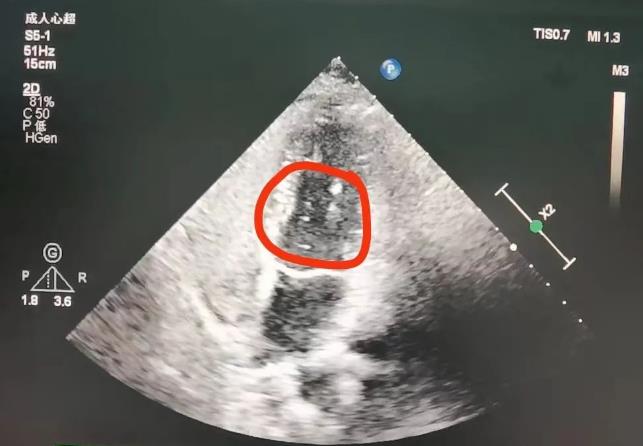

什么是经颅发泡试验?

“经颅发泡试验”

有什么意义及优点?

我院“经颅发泡试验”的优势